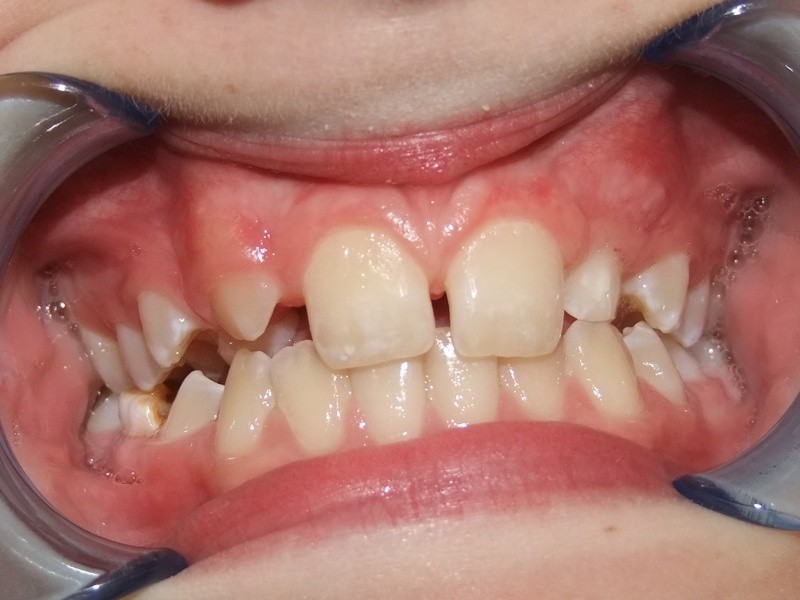

Voor behandeling

Maand 1-6: In de bovenkaak Bonded Hyrax, FaceMask

In de onderkaak volledig slotjes/brackets

TransForce met behulp van banden